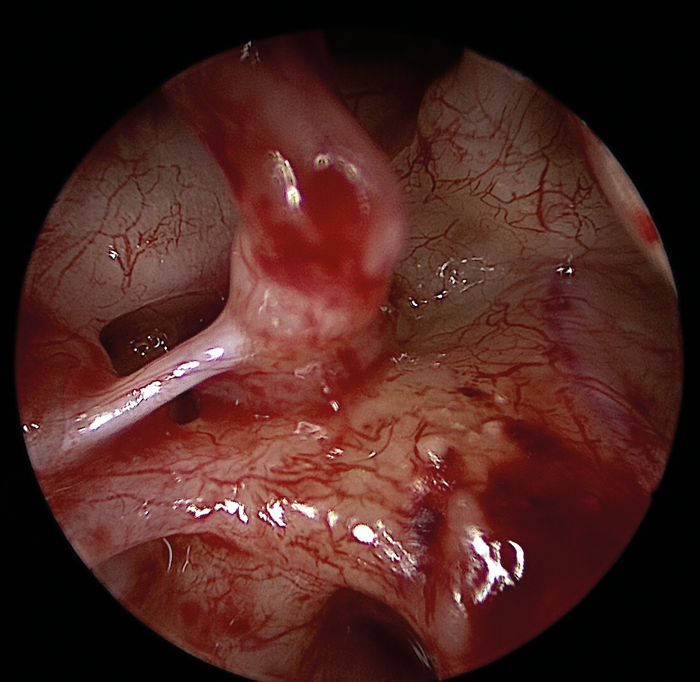

- Consider having an experienced colleague assist with suctioning when learning EES (Figure 2).

Figure 2: Three-handed technique.